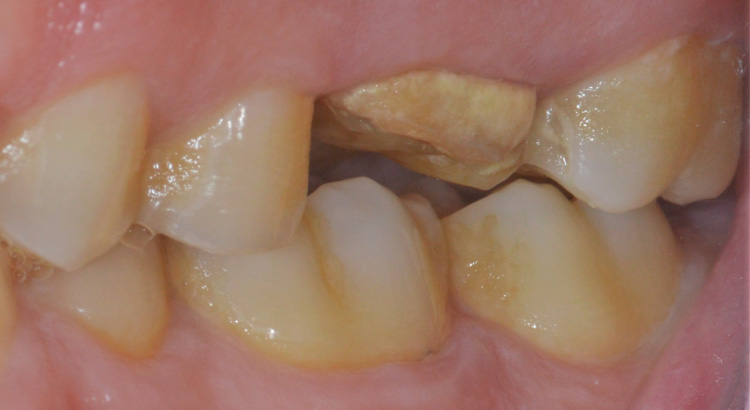

Protesi fissa su denti naturali

Il paziente presentava carie su tutti e tre gli elementi del settore posteriore, fondamentali per una corretta masticazione. La carie aveva portato ad una grave compromissione degli elementi, dolore dentale e il paziente masticava solo dall’altro lato. Grazie al trattamento endodontico e l’utilizzo delle nuove ceramiche è stato possibile ristabilire l’estetica e soprattutto la funzione masticatoria di quel lato.